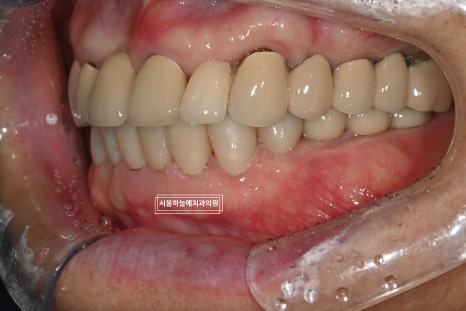

최종적으로 위아래 앞니

아래 양쪽 어금니 임플란트 보철까지

모두 안정적으로 마무리되었습니다.

처음 내원 당시와 비교하면

교합, 기능, 심미 모두에서 큰 변화가 있었고